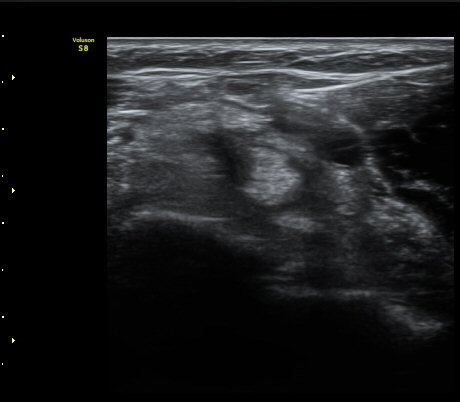

À̵ιڱ٠ÈûÁÙ Á¾´Ü¸é°Ë»ç¿¡¼­ ÈûÁÙÀÌ Àú¿¡ÄÚ°í °üÂûµÇ°í ÈûÁÙ ÁÖº¯ÀÇ ¼ö¾×Àú·ù°¡

¾Ö¸ÅÇÏ°Ô °üÂûµÈ´Ù(±×¸² 7). ŽÃËÀÚ ±ÙÀ§ºÎ¸¦ ÇǺÎÂÊÀ¸·Î ´©¸£´Ï ÈûÁÙÀÌ °í¿¡ÄÚ·Î

°üÂûµÇ°í ¼ö¾×Àú·ùµµ ¶Ñ·ÈÇÏ´Ù(±×¸² 8).